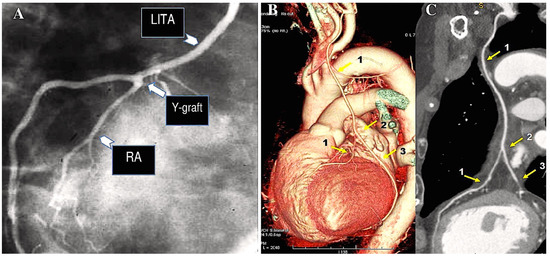

As a general principle, the surgeon advocates proximal anastomosis to the anterior portion of ascending aorta. Proximal anastomoses for individual conduits are achieved through the use of a suture to affix the graft end to side to an aortotomy in the proximal ascending aorta. A circular aperture measuring 3 mm in diameter is created in the aortic wall using a punch. The graft is then secured directly to the aorta using 7/0 Prolene sutures (Figure 1A,B).

The illustration depicts a coronary artery bypass graft (CABG) procedure utilising radial artery (RA), saphenous vein grafts (SVGs), and left internal thoracic artery (LITA) (A,B). (A): The SVGs have been anastomosed to the posterior descending artery branch of the right coronary artery (1) and to the obtuse branch of the left coronary circumflex artery. The proximal anastomosis is secured on the ascending aorta (yellow arrow). The LITA has been anastomosed to the left anterior descending artery (LAD). (B): The RA (2) is anastomosed distally on the right coronary artery and proximally on the ascending aorta (yellow arrow), while the LITA is anastomosed on the LAD. Note that the venous graft size is greater than the arterial graft size.

The RA conduit can be employed for sequential revascularisation and sutured as Y-graft to LITA (Figure 4A). Moreover, it is considered to be a prime location for performing proximal anastomosis on an additional RA conduit (Figure 4A). Such conduits may comprise an additional radial artery graft or a free RITA (Figure 4B,C).

The illustration depicts a CABG procedure utilising bilateral internal thoracic arteries anastomosed with Y-graft technique (A–C). (A): Conventional angiogram demonstrates the patency of the RA. The radial artery is employed as a Y-graft technique (LITA-RA-Y) for sequential anastomoses. (B,C): The Y-graft technique (LITA-RITA-Y) is utilised on the left anterior descending artery (LAD) and on the second marginal branch. 1. LITA-LAD; 2. LITA-RITA-Y; 3. RITA-second marginal branch. Abbreviations: LAD, left anterior descending; LITA, left internal thoracic artery; RA, radial artery; RITA, right internal thoracic artery.